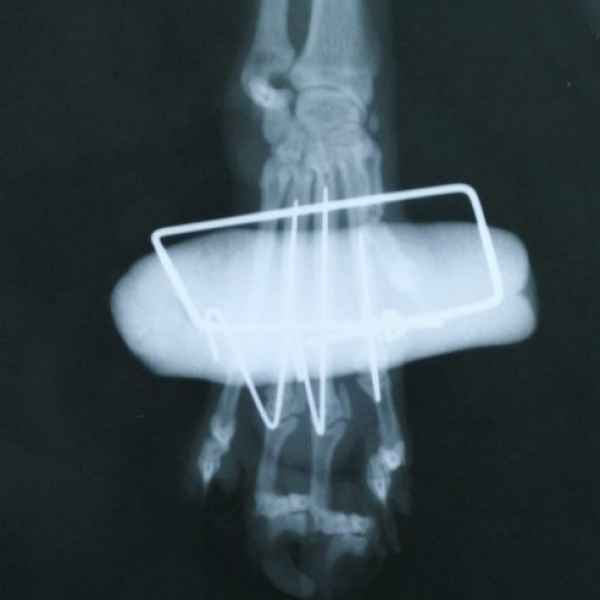

Вот что значит неудачно спрыгнуть с дивана. Это рентгеновские снимки одного из наших пациентов. Сначала хозяева обратили внимание на хромоту, а потом поняли, что у питомца очень болит лапа. Ещё бы не болело - поперечный перелом костей предплечья. Операция, установка DCP-пластины, восстановление, и он снова активный и жизнерадостный.

Этот пациент поступил к нам с кусаной раной левой грудной конечности После рентгенологического исследования обнаружили перелом костей предплечья. Сложность операции заключалось в том, что дистальный отросток лучевой кости был очень коротким. Хирургом нашей клиники было принято решение установить блокируемую lcp пластину. В данный момент пациент полностью восстановился..

Этот пациент поступил к нам после падения с 14 этажа. На основании комплекса исследований ,была установлена полиорганная недостаточность, перелом головки бедренной кости и трех пястных костей. Прием причинял сильную боль ,ведь был перелом нижней челюсти. Нами было принято решение по установке эгофагостомы. Ежедневно проводилась инфузионная терапия и только после полной стабилизации животного была проведена хирургическая операция по восстановлению костей.